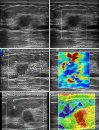

Figure 4

Images of an irregular breast lesion in a 42-year-old woman with low echo and no flow. The senior physician classified the lesion as BI-RADS 4b, while the intermediate-level and junior physicians classified it as BI-RADS 3. The lesion’s A'min 1.0 (Cs) and B/A' 0.5 are 1.15 m/s and 5.75, respectively. Both elastography scans give a result of malignant. After the addition of dual-mode elastography, the intermediate-level and junior physicians reclassified the lesion as BI-RADS 4a, and the pathological result was invasive nonspecific carcinoma.